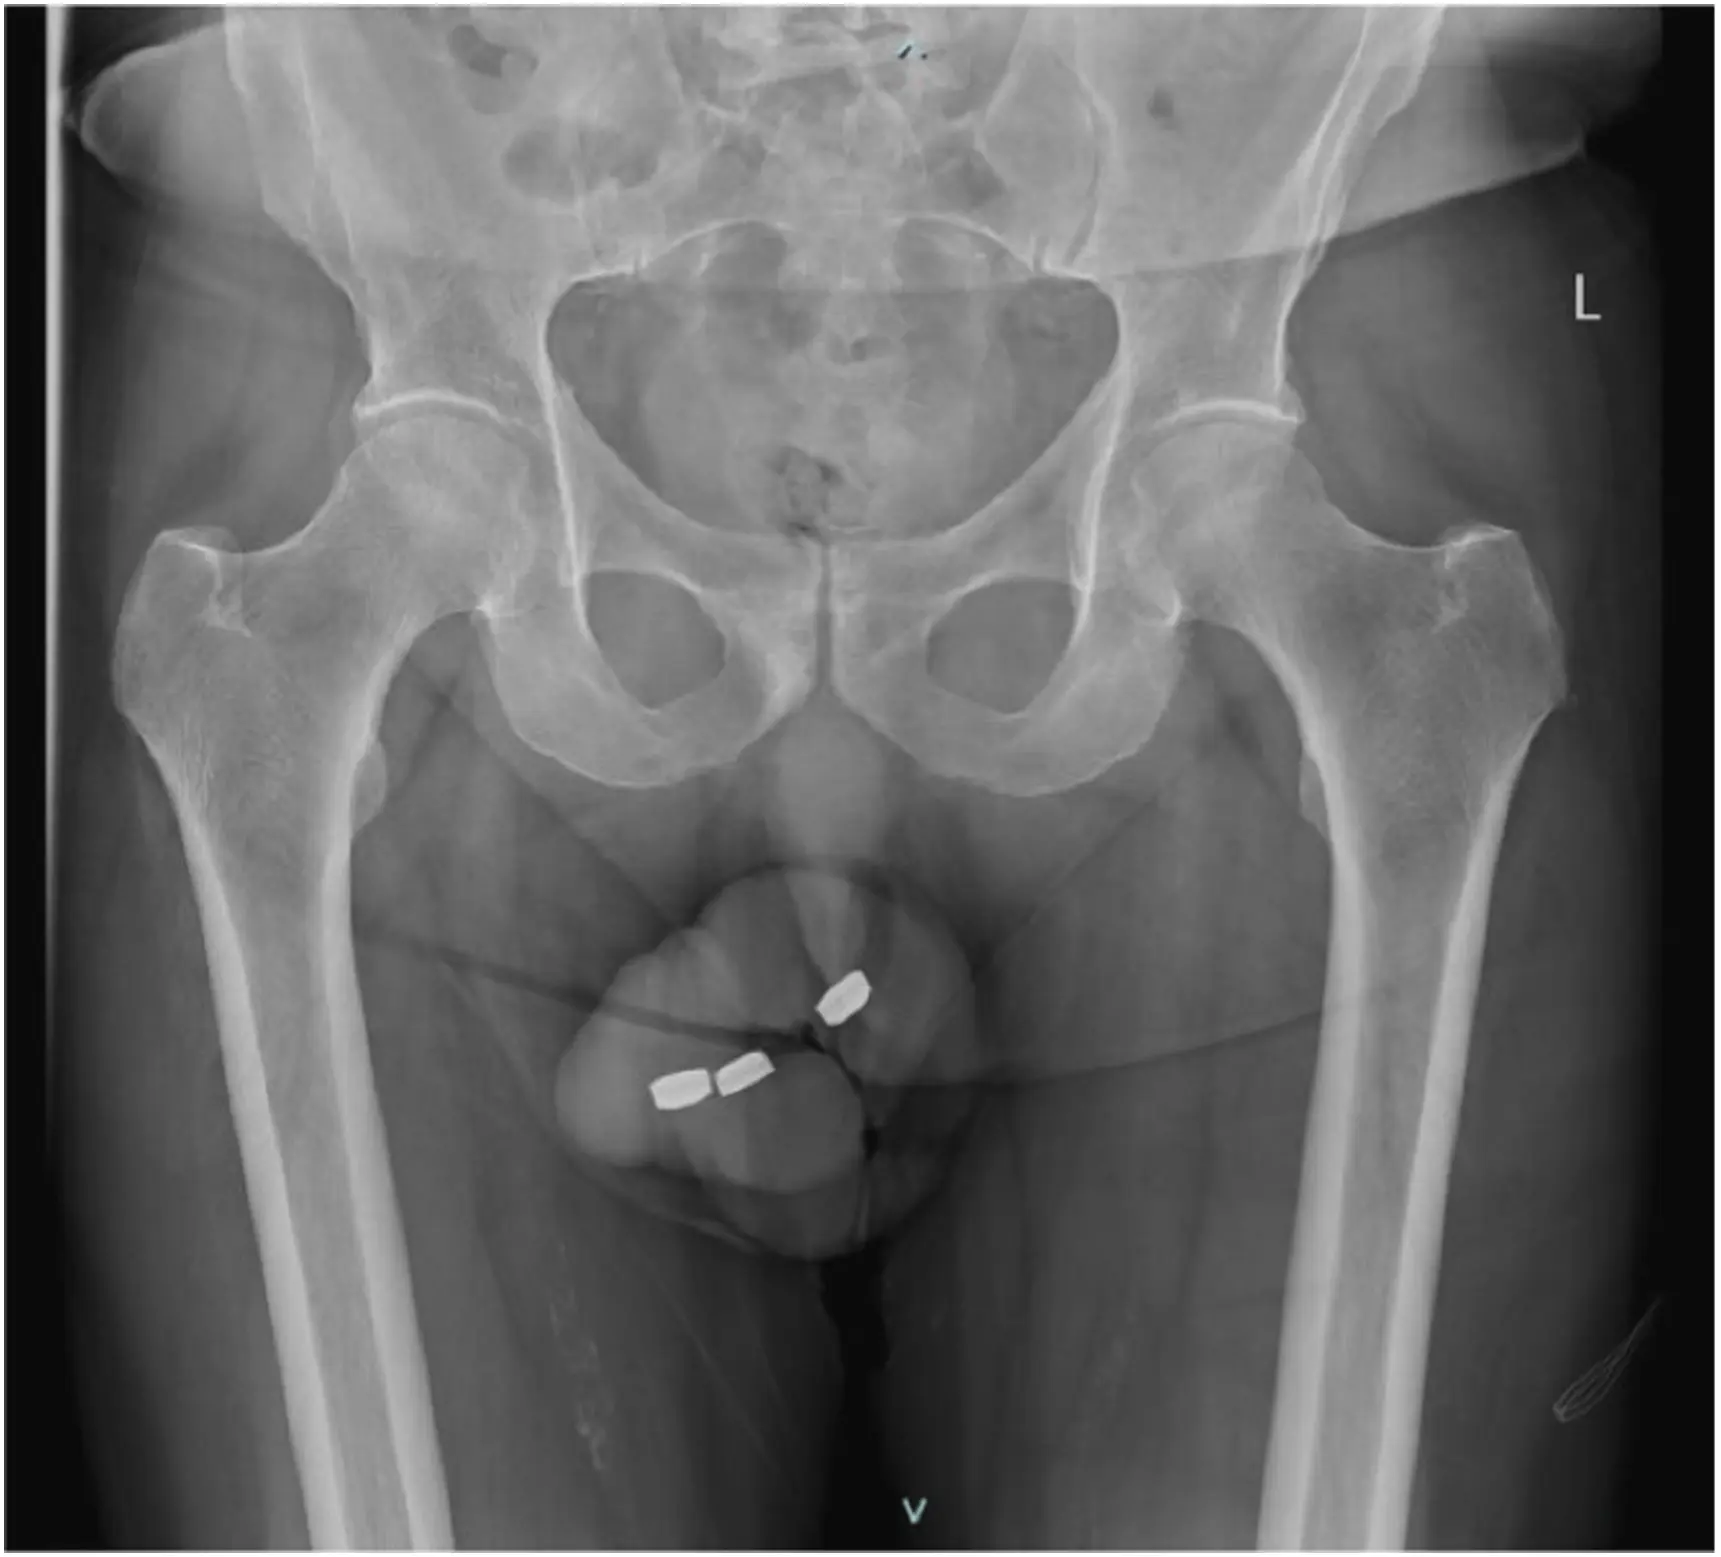

Un coup de jus pour booster sa vie sexuelle ? Le dernier numéro de la revue médicale Urology Case Reports rapporte l'histoire d'un Australien de 73 ans qui s'est présenté aux urgences pour une raison somme toute assez... électrisante. Pour "s'auto-satisfaire" sexuellement, l'homme a eu la drôle d'idée de s'insérer trois piles boutons de 1,3 cm de large chacune dans l'urètre.

"À notre connaissance, il s'agit du premier cas signalé de nécrose urétrale avec insertion de piles boutons", notent les auteurs dans leur étude de cas. L'équipe médicale a alors tenté de retirer les batteries à l'aide d'une pince, sans succès. Les médecins ont donc dû se résoudre à effectuer une lourde opération chirurgicale. "Toutes les piles extraites étaient recouvertes d'une substance ressemblant à du goudron noir", est-il également précisé dans l'étude. Après l'opération, "des brûlures étendues de l’urètre antérieur du pénis ont été notées".